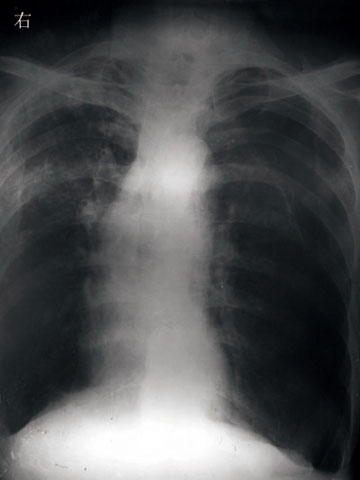

患者:男  60岁  咳嗽,胸痛呼吸困难10天。既往慢支炎肺气肿。

1)右上继发性肺结核。2)慢性支气管炎,肺气肿。3)左侧气胸。

支持,左侧肋膈角也变钝。片子质量太差。

右上肺继发性结核。慢支肺气肿。左肺是否气胸看不清,条件太高了。双肋膈角变钝意义应该不大

右上肺陈旧性肺结核,慢支炎、肺气肿,左侧气胸,片子质量差,最好重照。